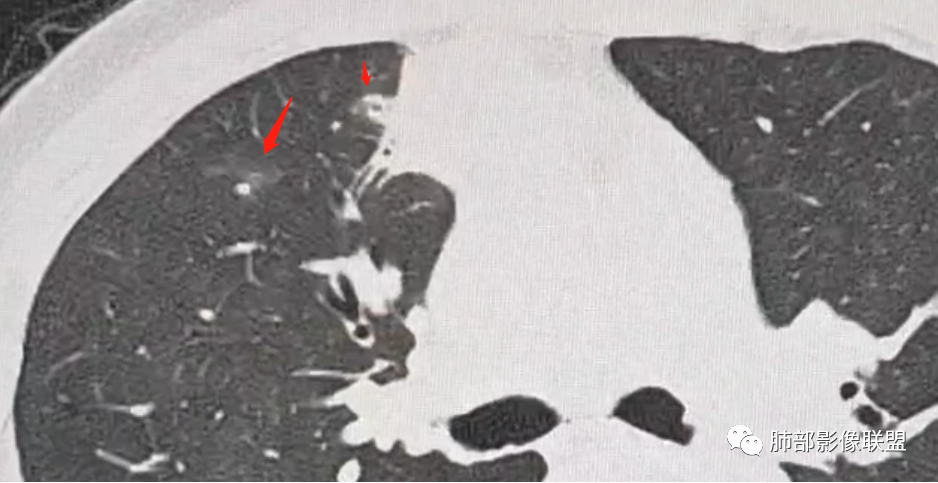

1

红箭-支气管分叉间条形高密度